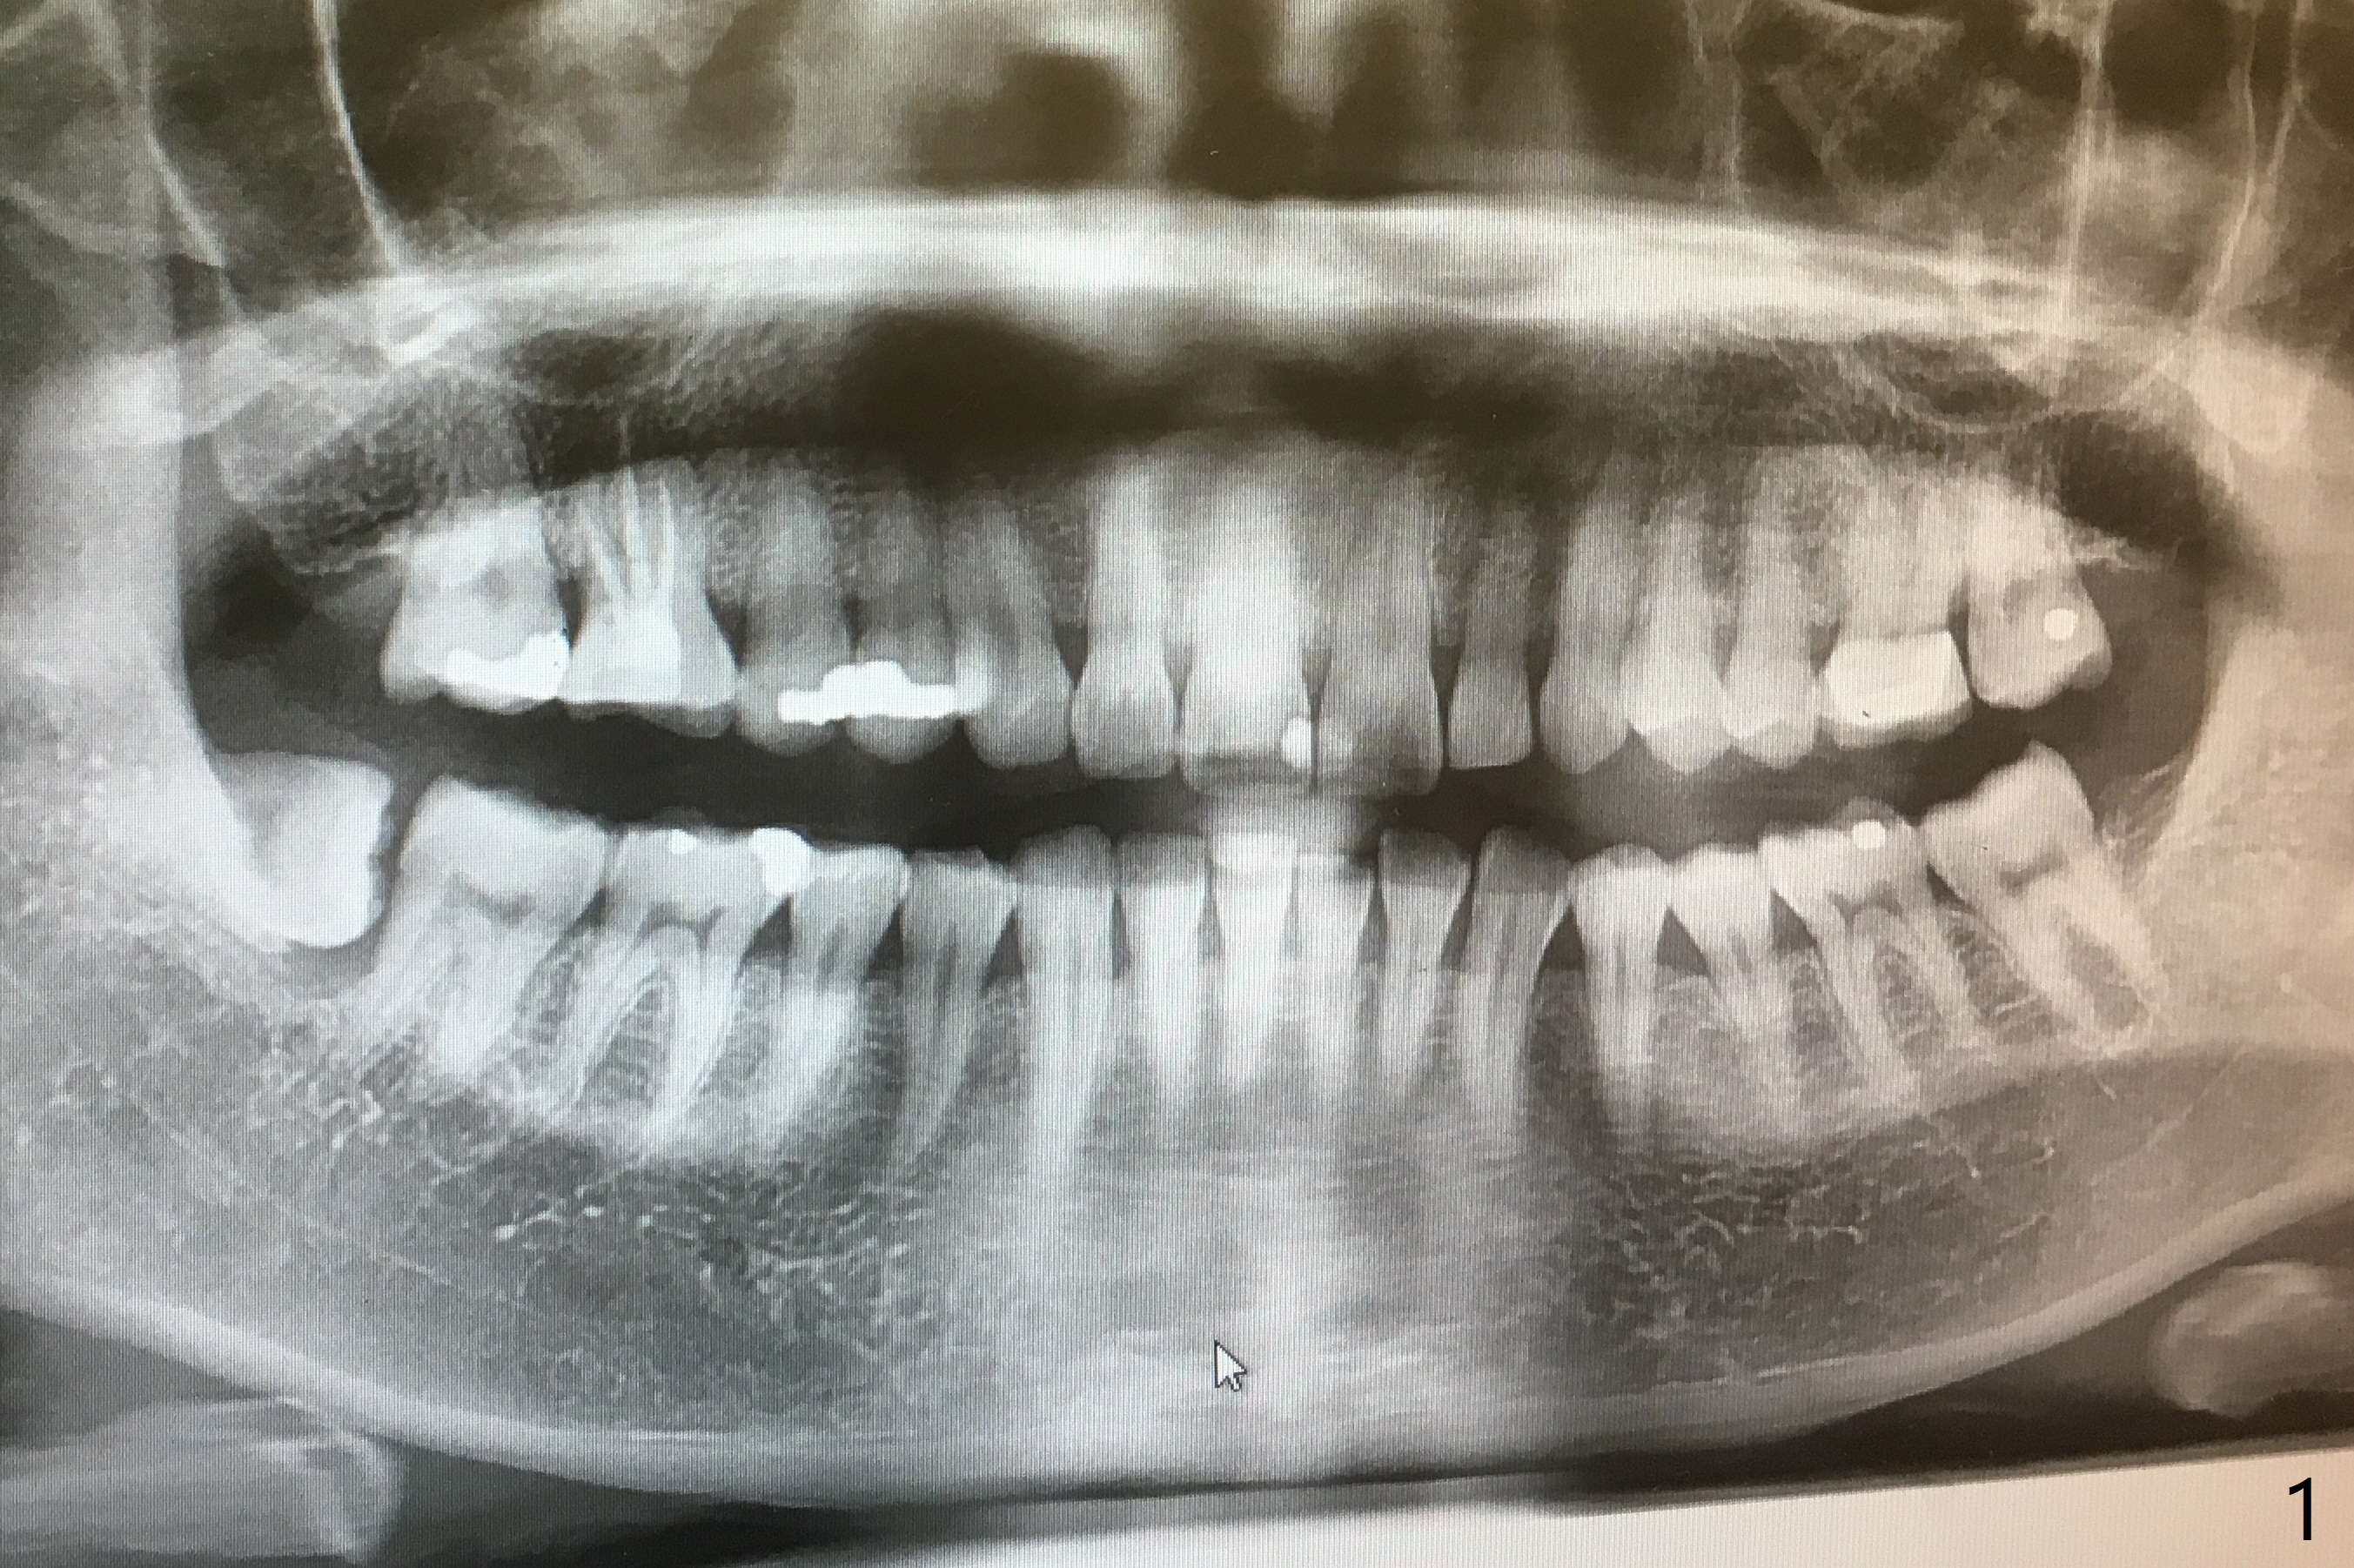

A 52-year-old woman requests extraction of the tooth #32 (Fig.1). With Local anesthesia, hockey-stick incision is made, reflected mucoperiosteal flap, buccodistal trough, sectioned, straight elevator/forceps removal, curette, Piezo 31 distal, copious irrigation, placed a 10x20 mm OsteoGen Plug into bony defect, 4-0 plain gut suture, 2x2 gauze, hemastatic. The wound heals with apparent bone formation 8 months postop (Fig.2).